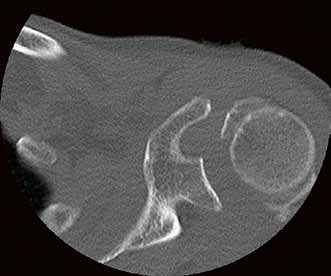

Die Klinik verfügt über 14 Computertomographen (CT), zwölf Magnetresonanztomographen (MRT) sowie zahlreiche Ultraschallgeräte. Allein am Campus Benjamin Franklin führen die Radiologen an sieben Tagen die Woche je zwischen 50 und 60 CT Untersuchungen täglich durch. Seit knapp drei Monaten steht ihnen dazu der neue 160-Schicht-Low-Dose-CT Aquilion PRIME zur Verfügung. Ein weiterer Aquilion PRIME sowie ein 640-Schicht-Volumen-CT Aquilion ONE ViSION EDITION wurden am Campus Mitte installiert. „Als wir nach einem neuen CT gesucht haben, war klar, dass dessen Ausstattung allen universitären diagnostischen Anforderungen gerecht werden muss", erklärt Dr. Stefan Niehues, Radiologe und Oberarzt der Klinik für Radiologie am Campus Benjamin Franklin.

„Mit dem neuen CT Aquilion PRIME können wir das komplette radiologische Spektrum der Charité abdecken. „Die gesamte Polytrauma-Diagnostik über die Akutversorgung bis hin zur Neuroradiologie und Diagnostik bei jungen Menschen führen wir mit dem Aquilion PRIME durch."

Dass sich Dr. Niehues und sein Team in einem langen und aufwendigen Entscheidungsprozess für das innovative CT aus dem Hause Toshiba ausgesprochen haben, hat mehrere Gründe. „Ich war Sofort beeindruckt von der Rechnergeschwindigkeit", sagt Dr. Niehues. Die Rekonstruktion der Bilder erfolge am Aquilion PRIME in einem Bruchteil der Zeit, die früher vergangen sei, bis das CT die komplette Bildserie samt Rekonstruktionen erstellte. „Heute haben wir alle Bilder nach wenigen Minuten", weiß Dr. Niehues, er hat das Intervall zwischen Untersuchung, Scan und Rekonstruktion aus Interesse selbst gestoppt. Früher sei das Polytrauma-Team samt Patient dann oft schon längst wieder verschwunden gewesen. „Die ständige Entscheidung zwischen schneller Rekonstruktion und einer kompletten Serie in dünnen Schichten und guter Bildqualität fand ich belastend - mit dem Aquilion PRIME hat sich das Problem gelöst", resümiert Dr. Niehues.

Neben der Rechnergeschwindigkeit lautet das Schlüsselwort bei dem neuen Gerät „Adaptive Iterative Dosis-Reduktion (AIDR 3D)". „Dieser mathematische Algorithmus erlaubt es uns, mit einem Bruchteil der Dosis zu arbeiten, die wir bisher für die erforderliche Bildqualität benötigt haben", weiß der Radiologe.

„Durch die Spitzentechnologie können wir bei gleich hoher Bildqualität die Dosis an Röntgenstrahlung bei vielen Untersuchungen auf ein Drittel reduzieren."